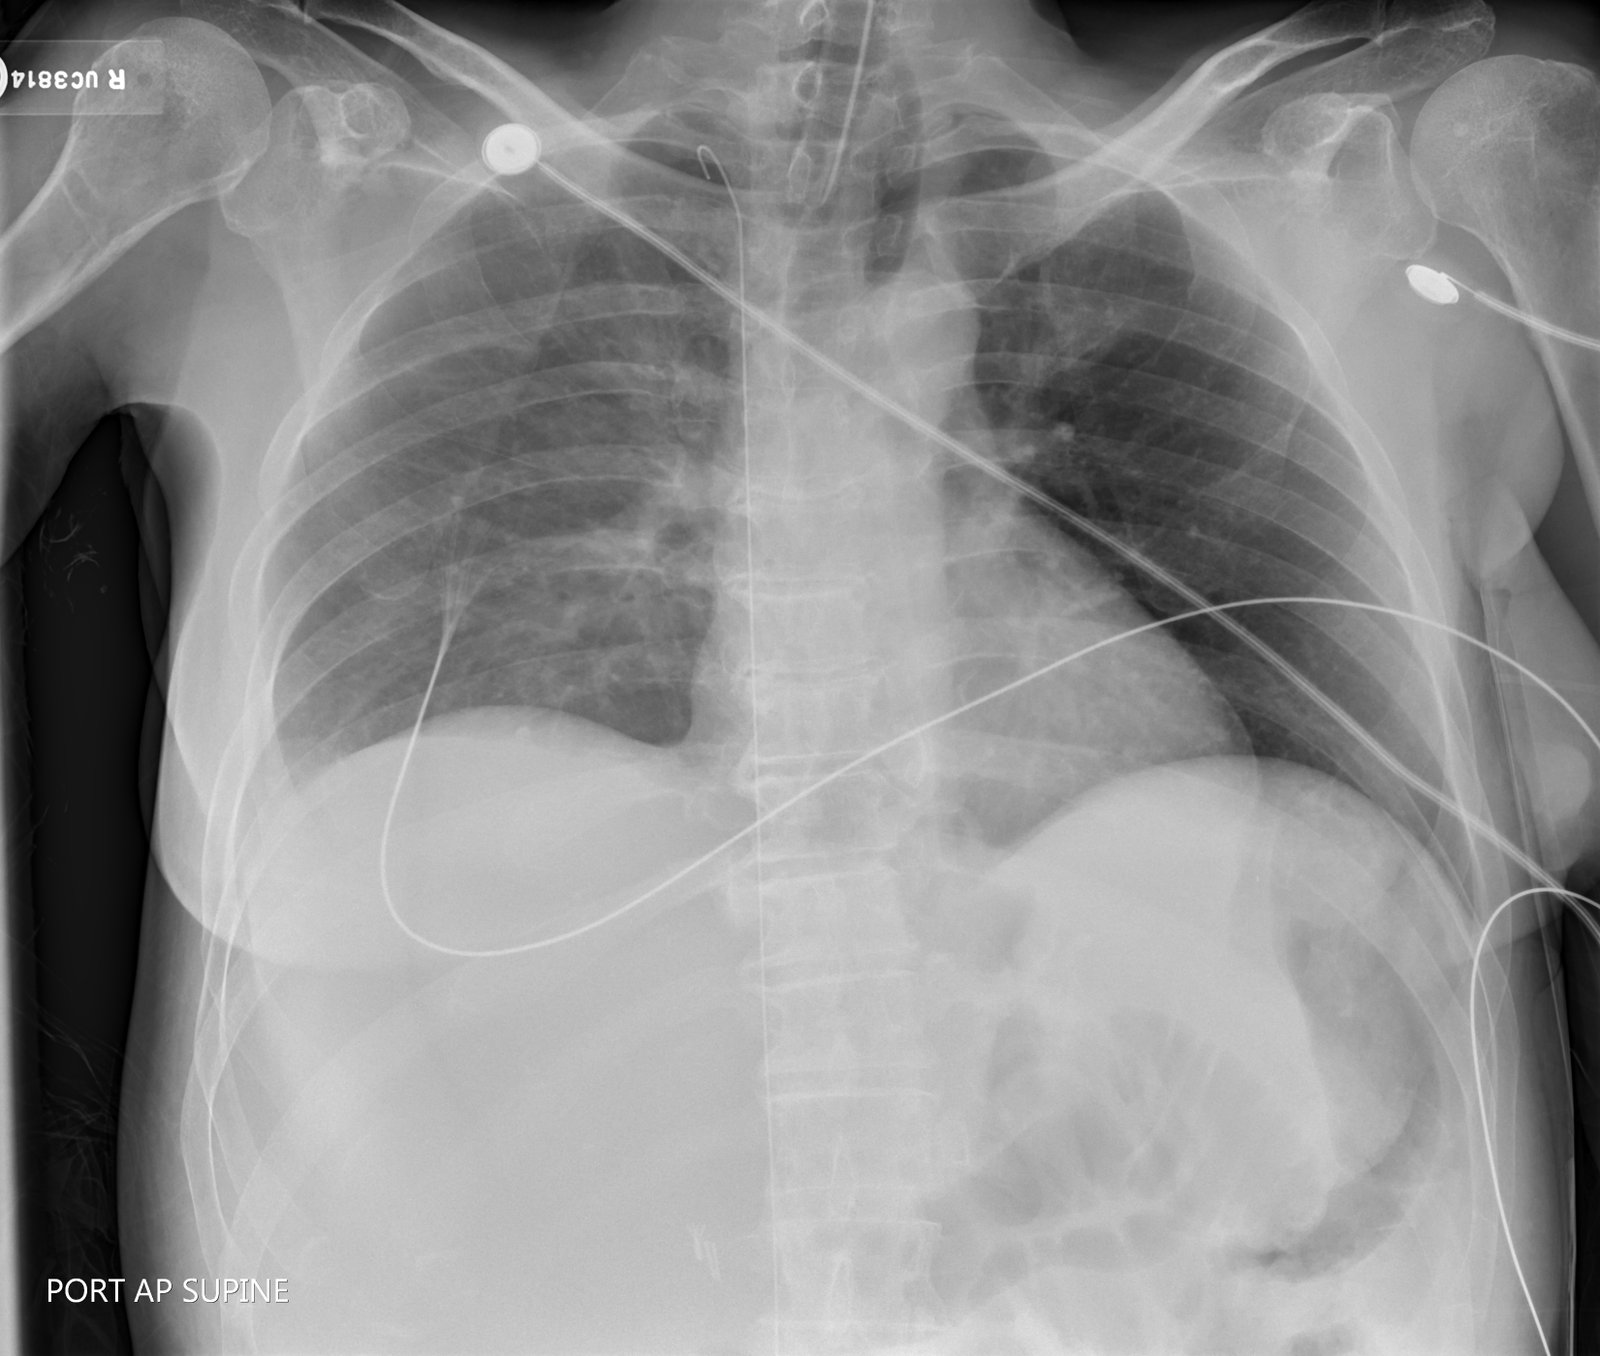

Significant findings:

Initial chest radiograph shows a guidewire in the inferior vena cava (IVC), superior vena cava (SVC), and right IJ veins.